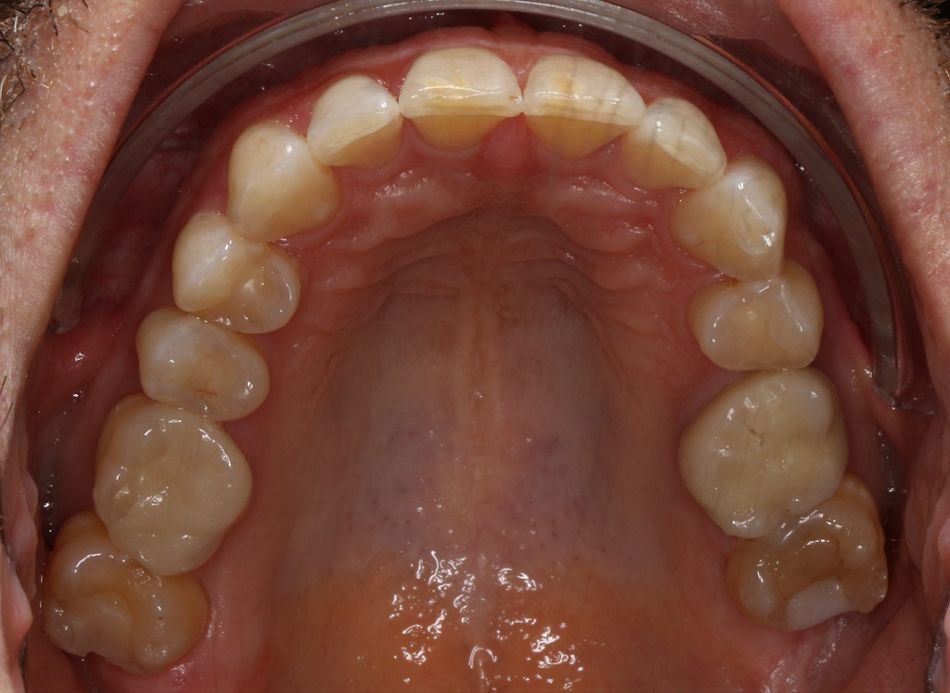

Ergebnis:

Dadurch war der Patient funktionell rehabilitiert, was eine Entlastung des Kiefergelenks, sowie der Kaumuskulatur zur Folge hatte [9]. Gleichzeitig wurden die inzisalen Schmelzkanten durch die freie Envelope of Function vor übermässiger Attrition geschützt [7]. Die aktive Mundöffnung stieg auf 42mm, passiv auf 50mm.

Foto Status nach Behandlung